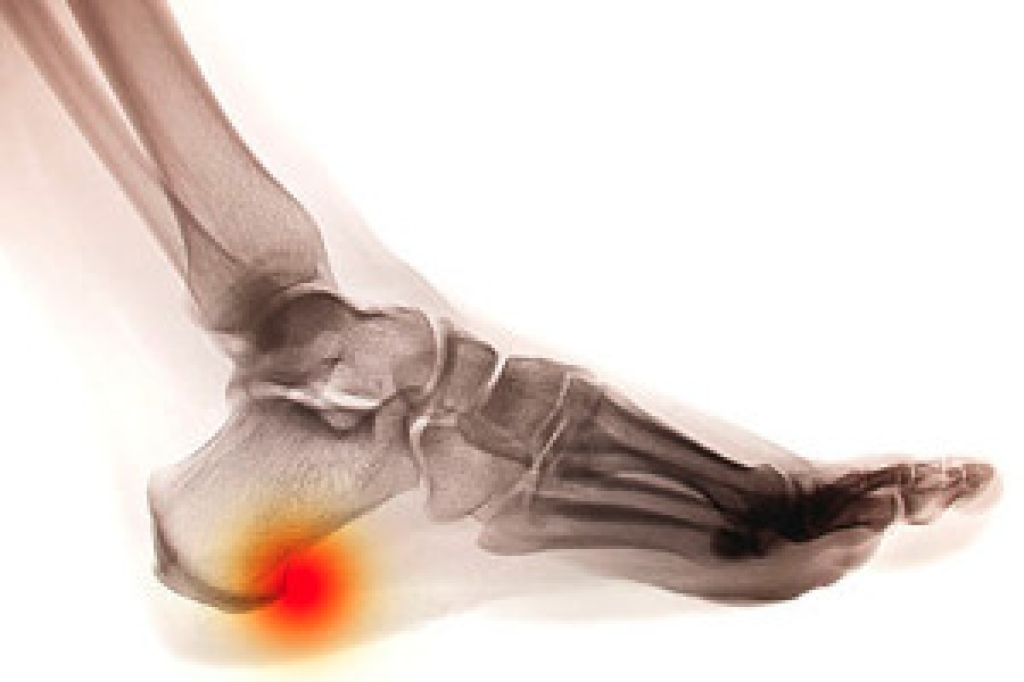

Heel spurs are bony growths that develop on the underside of the heel bone, typically as a result of prolonged stress or strain on the foot. The most common cause of heel spurs is plantar fasciitis, an inflammation of the tissue that connects the heel to the toes. Other factors that contribute to heel spurs include wearing improper footwear, obesity, repetitive activities that put pressure on the feet, and abnormal foot mechanics such as flat feet or high arches. While heel spurs themselves are often painless, they can lead to complications such as chronic pain, difficulty walking, and inflammation. In some cases, the spur may press on nearby nerves, causing sharp or shooting pain. If left untreated, heel spurs may limit mobility and interfere with daily activities, leading to long-term discomfort and reduced quality of life. If you have heel pain, it is suggested that you consult a podiatrist who can provide an accurate diagnosis and treatment solutions.

Heel spurs are formed by calcium deposits on the back of the foot where the heel is. This can also be caused by small fragments of bone breaking off one section of the foot, attaching onto the back of the foot. Heel spurs can also be bone growth on the back of the foot and may grow in the direction of the arch of the foot.

The pain associated with spurs is often because of weight placed on the feet. When someone is walking, their entire weight is concentrated on the feet. Bone spurs then have the tendency to affect other bones and tissues around the foot. As the pain continues, the feet will become tender and sensitive over time.